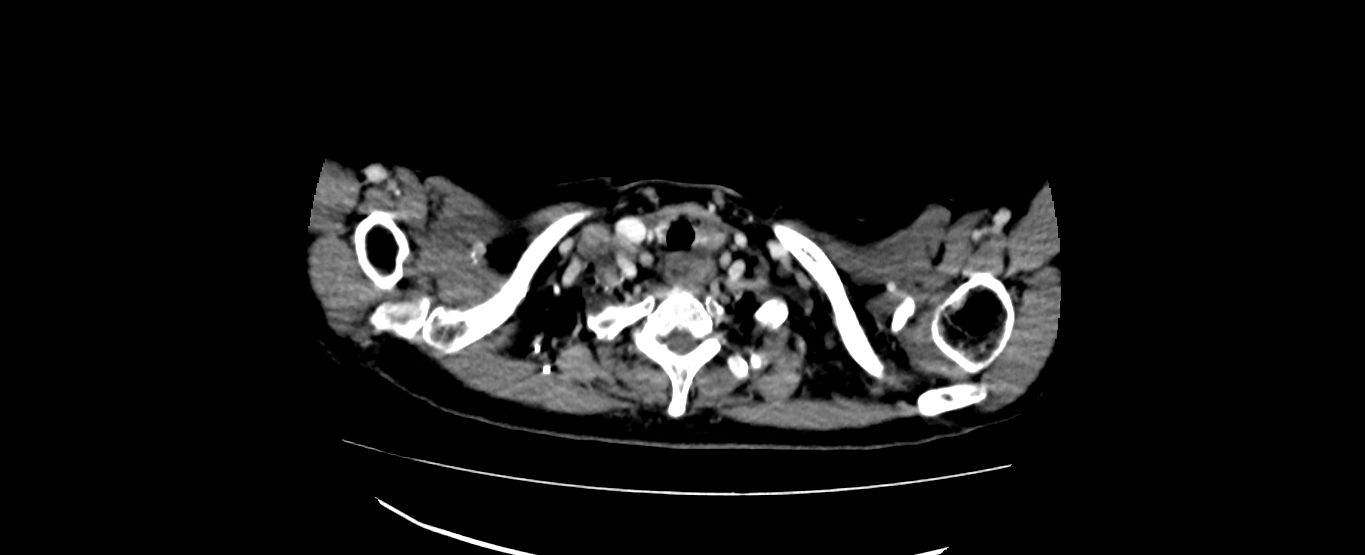

患者黄某某,女,56岁,食管中分化鳞癌患者,因吞咽困难检查发现食管癌,予以食管癌根治性调强放疗,巨大食管肿瘤消退明显,疗效良好,目前患者能够正常进食,体重逐渐恢复。

放疗前CT: